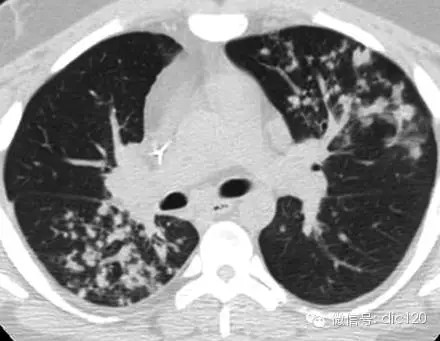

树芽征是指病变累及细支气管时,由于炎性渗出物或分泌物堵塞细支气管, CT表现为小叶中心分枝状线影和与其相连的细支气管横断面结节影,状如春天里挂满枝芽的”树”,即”树芽征”。是细支气管扩张、阻塞的特征影像之一。由Im等1993年首次报道,最初用来描述肺结核沿终末支气管扩散的征象,后来逐渐用于有类似征象的其它支气管疾病。CT尤其是高分辨CT(HRCT)能够很好的显示此征。

CT表现——在肺外围支气管的末梢呈现2~4mm大小结节与树枝状的高明电影。

意义:表明有小气道病变如:细支气管炎症、弥漫型细支气管炎级肺结核活动病灶或播散病灶等。